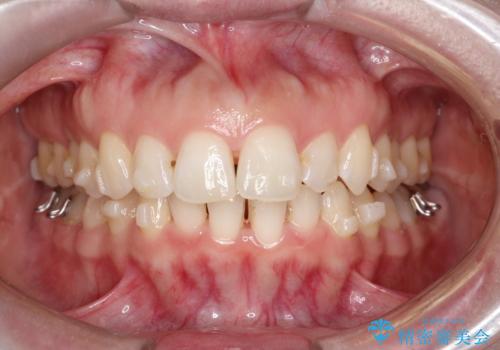

【インビザライン】前歯の凸凹を治したい。

- 前歯の凸凹を主訴に来院されました。

深い噛み合わせも同時に治療を行う計画を立て、インビザラインを使用して歯並びの改善を行うことができました。

叢生改善のために遠心移動とIPRを行なっています。